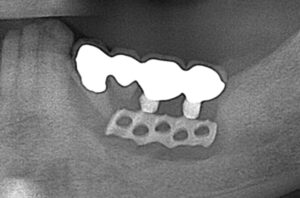

ブレードインプラント

こちらが1960年代に使われた板状で窓が開けられているブレードインプラントの実際の写真になります。

レントゲン像では大きな骨吸収が見られます。

来院時には、揺れが大きく、痛みもあったため撤去を行いました。

現在は吸収されていた骨も治癒し、元々のインプラント部位は入れ歯を作製し使用されています。